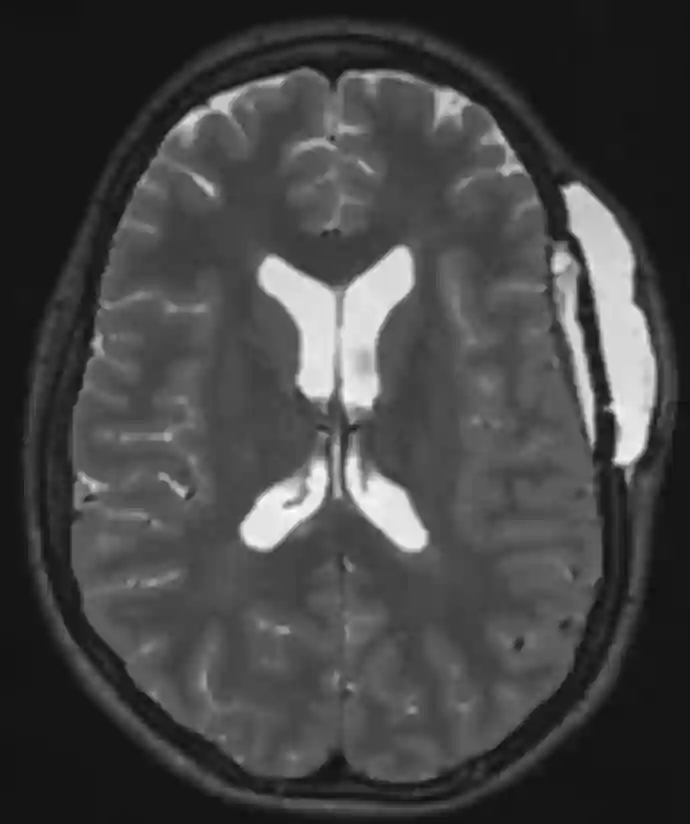

Bildgebung

Ein Liquorkissen kann durch die klinische Untersuchung diagnostiziert werden als auch in einer CT oder MRT Bildgebung dargestellt werden.